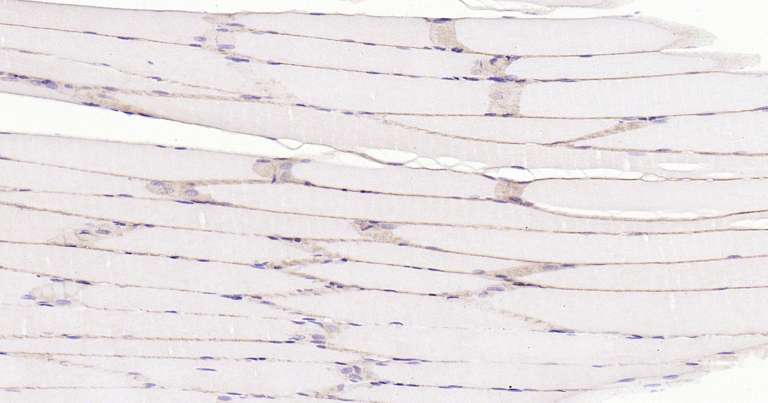

Immunohistochemical analysis of paraffin embedded rat skeletal muscle tissue slide using IHC0260R (Rat Dystrophin IHC Kit).